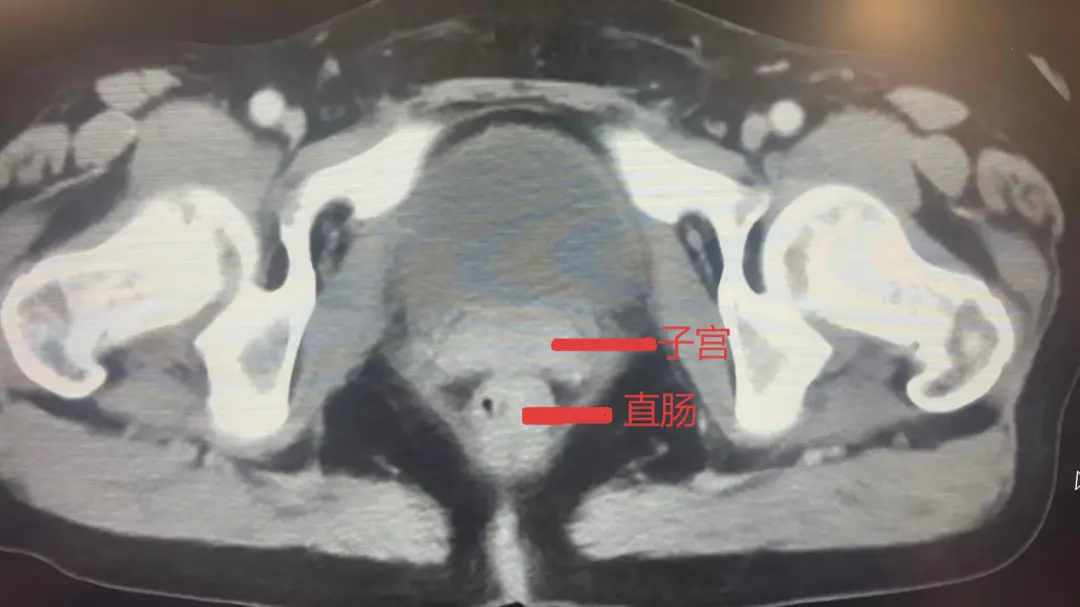

患者弓女士此前确诊直肠恶性肿瘤,进一步检查发现肿瘤已侵犯子宫及小肠,于医院肿瘤科行化疗+靶向治疗,但内科治疗出现耐药,患者持续便血,导致贫血难以纠正,不仅生活质量差,更时刻危及生命。肿瘤科郝淑兰主任及陈海富医师启动MDT,在医务科组织下,肿瘤科、普外科、妇科、麻醉科共同讨论病情,最终制定实施全麻下腹腔镜直肠肿瘤切除术+部分小肠切除术+子宫及附件切除术的联合手术方案。